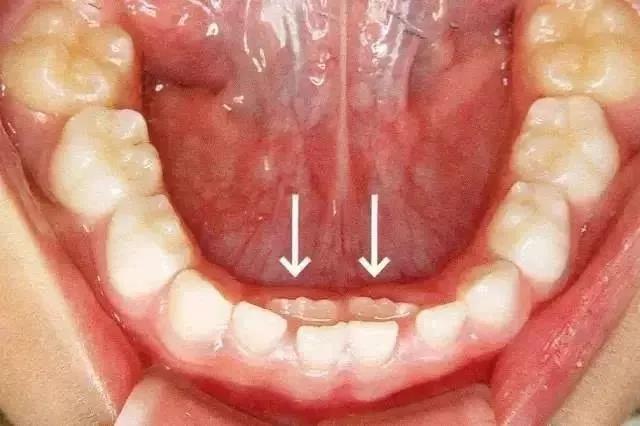

孩子直到8岁才开始有换牙迹象,但旧的乳牙依然 " 坚挺 ",没有脱落,下牙齿中间长出的两颗新牙,被挤成 " 倒八字 " 的形状,中间还产生了半颗牙的空隙,看上去就像两排异形牙,极影响美观。这可怎么办呀?

儿童换牙期,乳牙脱落和恒牙萌出关系十分密切。孩子六七岁时,乳牙就已经基本完成使命,自动脱落,随后恒牙逐渐萌出。但是,有些孩子恒牙已经长出来了,而相应的乳牙却迟迟不肯“退位让贤”,恒牙被迫“委曲求全”,从后面萌出,形成一前一后双排牙。在口腔医学中,这种情况被称为乳牙滞留。

“双排牙”一般在七八岁的孩子中最为常见,通常发生在下牙,也有上牙长双排牙的现象。